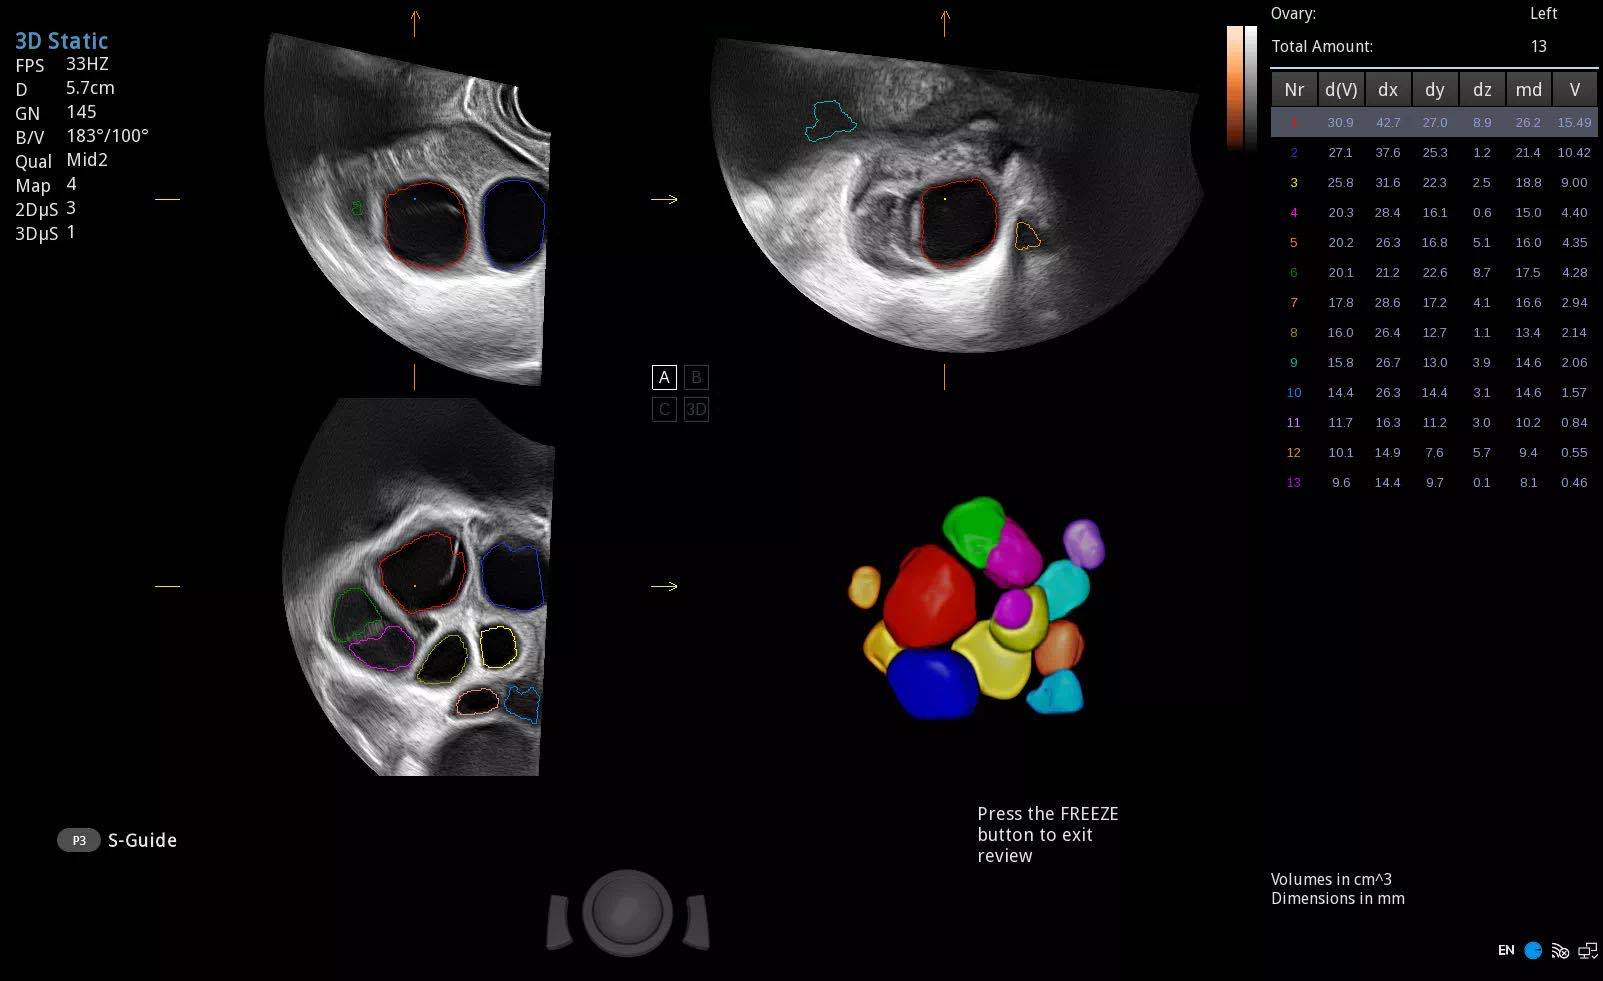

“针对患者的全面生殖健康评估,包括妇科疾病检查、输卵管通畅程度检查和卵泡检查等在内都是非常重要的”,梅登医生说。

在谈及未来医疗发展时,Harald Meden医生表示“人工智能为新时代的医学进步提供了更多可能,人工智能切实为临床工作提供了许多帮助。在公海贵宾会员检测中心超声智能功能的帮助下,我们将会为社区居民提供更好的服务。”